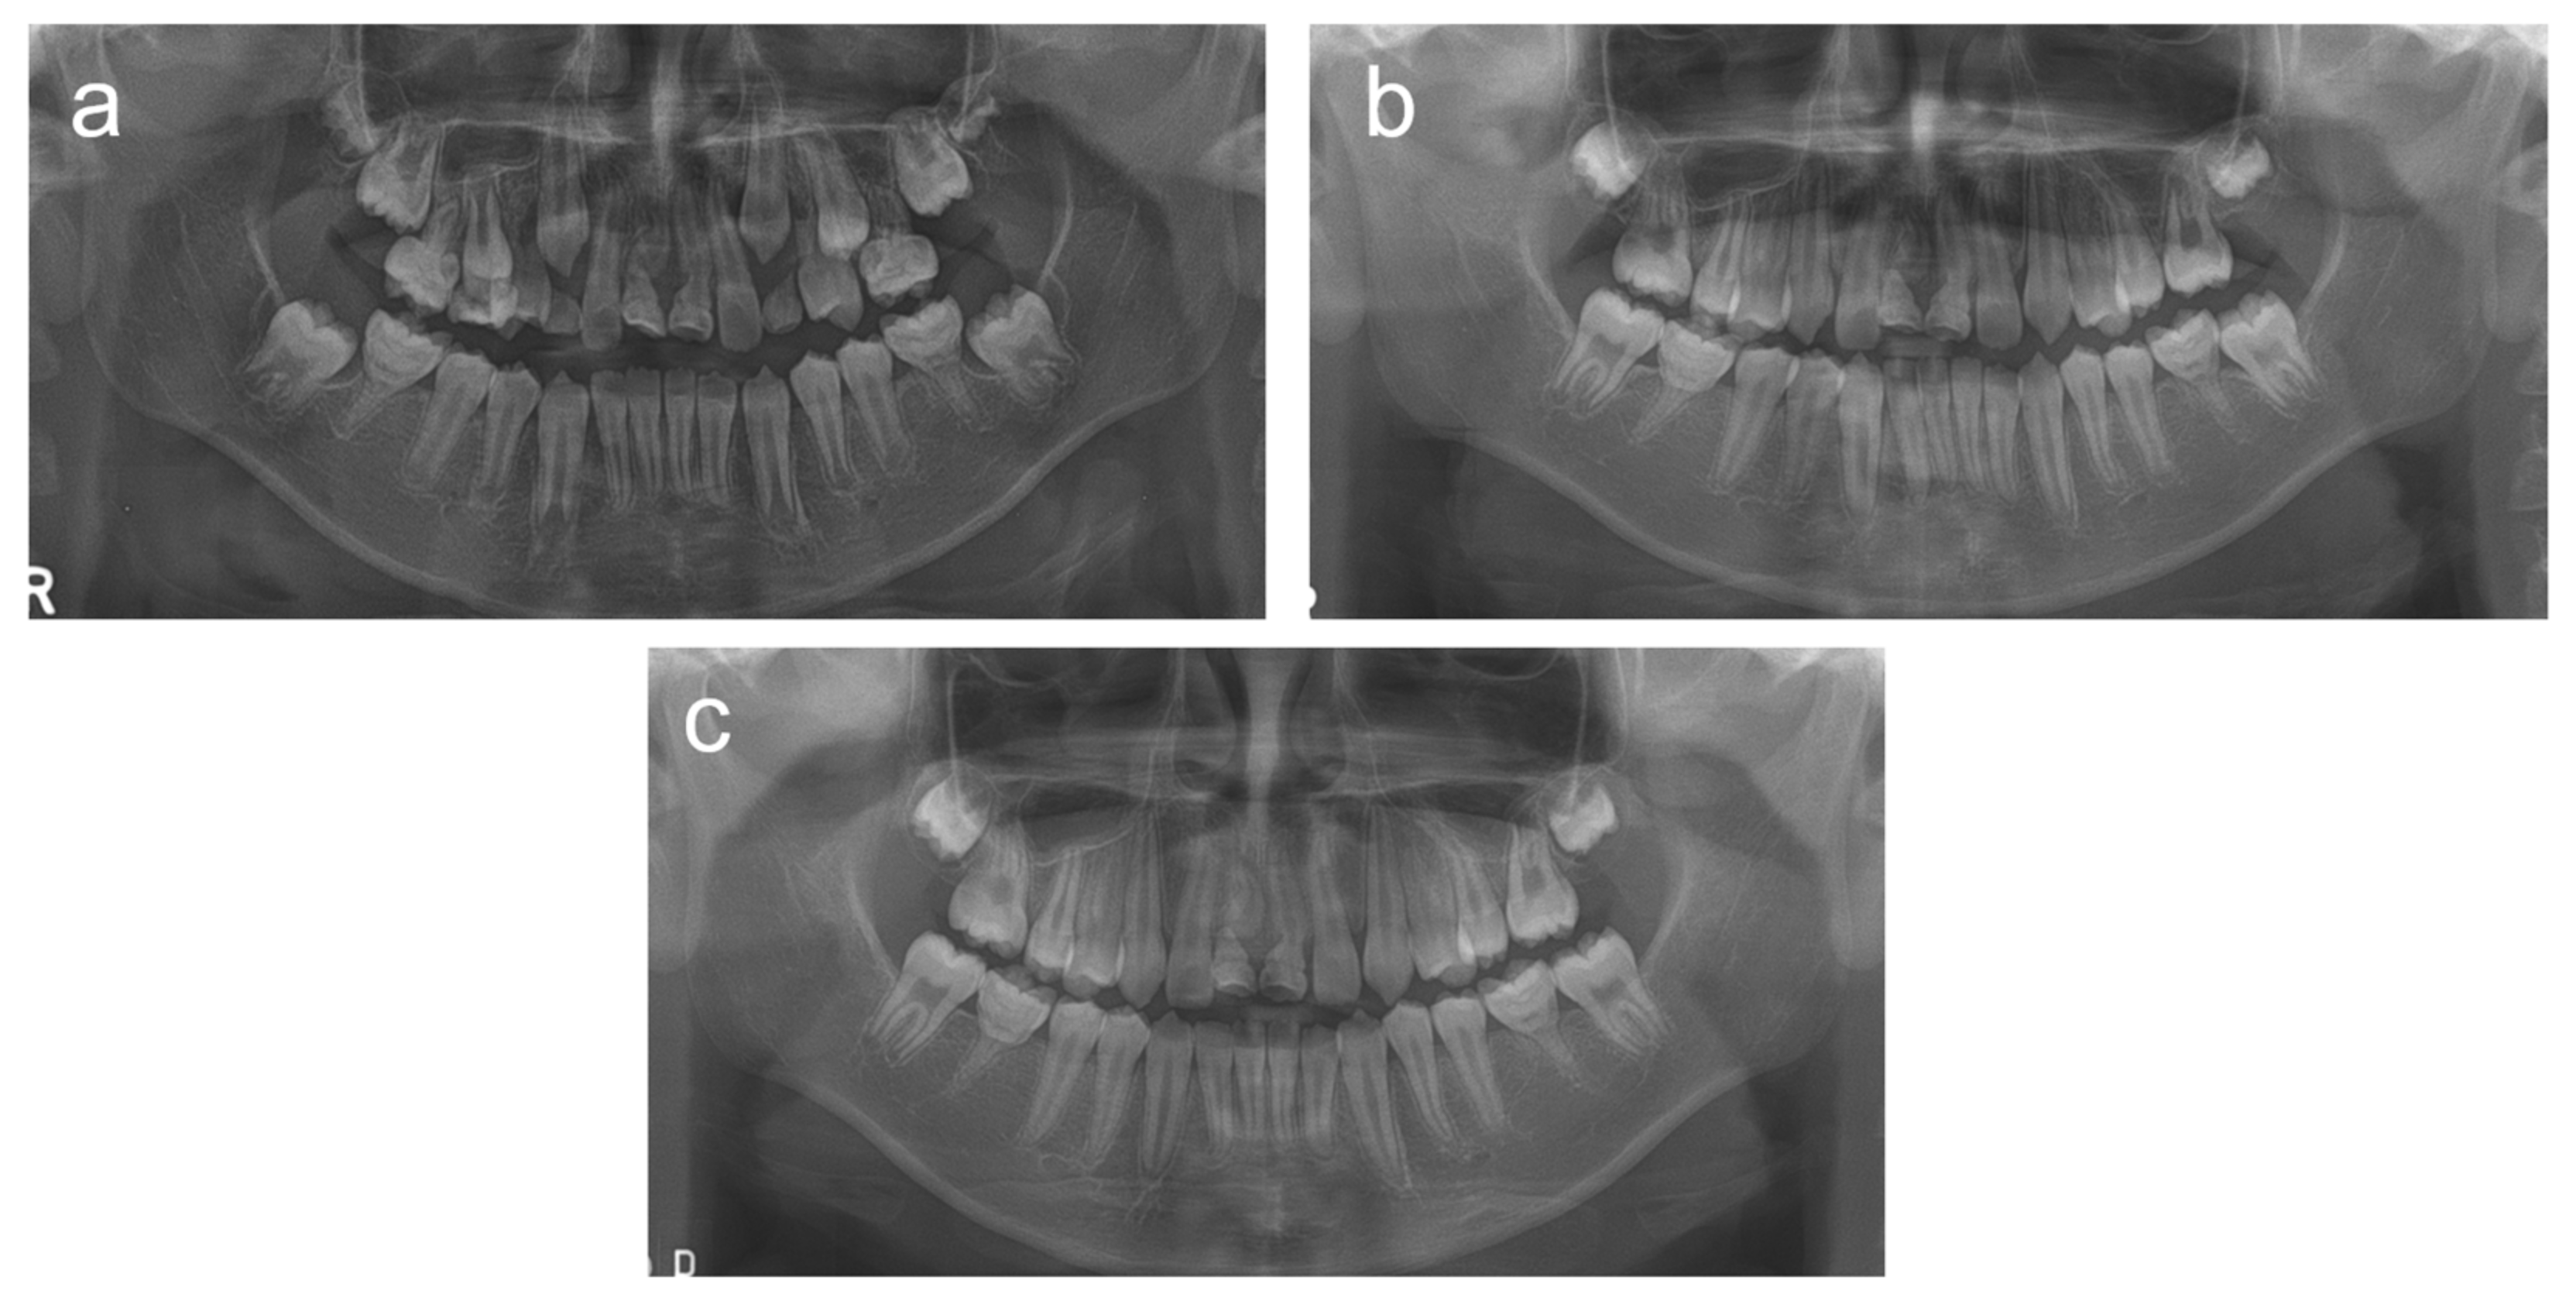

2.2. Case 2

2.3. Case 3

2.4. Case 4

2.5. Case 5